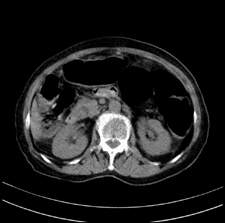

患者,女,75岁。腹痛,体黄5日,膝胸位时腹痛缓解。肝功能明日出来。彩超提示胆总管占位,未见血流信号。心电图提示s-t段改变。患者体质较弱,未能增强。

胆总管多发结石伴肝内外胆管轻度扩张。

胆总管上段,腔内有软组织密度影 ,ct值36-44hu。大家看有没有胆管癌的可能。

2楼所说胰腺内钙化不像,象脾脏血管的钙化